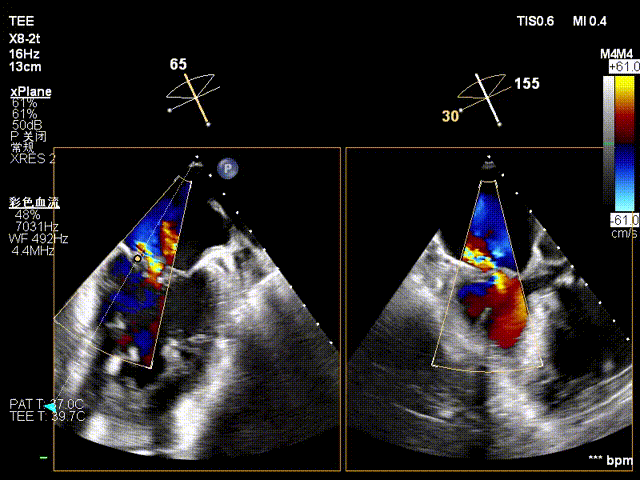

术前心超提示:

退行性二尖瓣反流(DMR),A2-A3脱垂伴连枷样运动(脱垂范围:17mm,连枷间距:7mm),P3脱垂,反流主要位于2-3区,MR重度4+(VC:6*17 mm),A3:18mm,P3:9mm,A2:24mm,P2:14mm,AP:32mm,二尖瓣口面积MVA约 5.6cm²,左房、左室明显扩大。

术前反流 术后反流